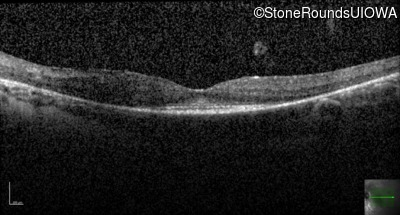

Optical Coherence Tomography - Left - 20/30 sc

Exemplar / OCT Stack

OCT Stack